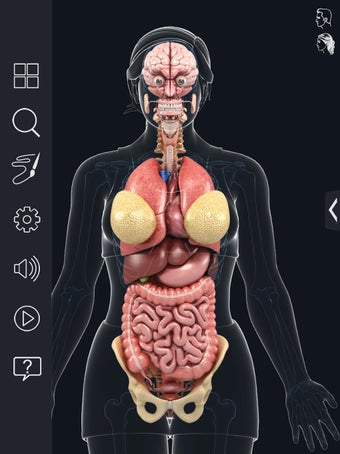

My Organs Anatomy es una aplicación de anatomía 3D gratuita desarrollada por Visual 3D Science para usuarios de Android. Esta aplicación proporciona un modelo 3D altamente realista de los órganos humanos que se puede girar 360°, acercar y alejar, y ver desde cualquier ángulo. La aplicación está diseñada para proporcionar una mirada detallada a la anatomía de los órganos humanos y ofrece varias características para ayudar a los usuarios a explorar y aprender.

La interfaz fácil de usar de My Organs Anatomy permite una navegación sencilla, lo que facilita la selección, rayos X, ocultación y visualización de órganos individuales. La aplicación también incluye un modo de animación, opciones de búsqueda y un panel de información que proporciona información relacionada. Además, la aplicación ofrece pronunciación de audio para todos los términos anatómicos, e incluso los usuarios pueden dibujar o escribir en la pantalla y compartir capturas de pantalla.

En general, My Organs Anatomy es una gran aplicación para estudiantes de medicina y cualquier persona que quiera explorar la anatomía de los órganos humanos en detalle. Con sus gráficos de alta calidad y numerosas características, esta aplicación proporciona una excelente experiencia de aprendizaje para los usuarios.